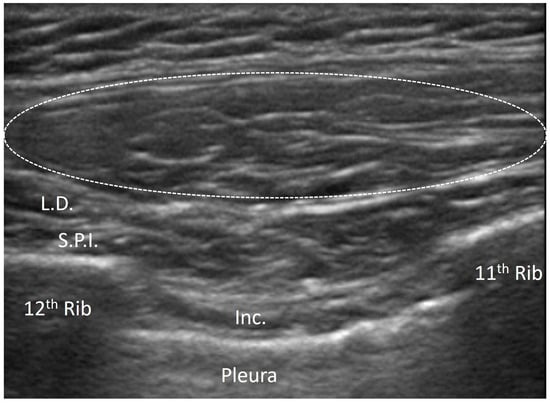

3.4.2. Elastofibroma Dorsi

- Hartavi, A.; Duman, A.; Yetişgin, A.; Ekiz, T. Elastofibroma dorsi: Multimodal imaging. PM&R 2014, 6, 960–962. [Google Scholar] [CrossRef] [PubMed]

- Battaglia, M.; Vanel, D.; Pollastri, P.; Balladelli, A.; Alberghini, M.; Staals, E.L.; Monti, C.; Galletti, S. Imaging patterns in elastofibroma dorsi. Eur. J. Radiol. 2009, 72, 16–21. [Google Scholar] [CrossRef] [PubMed]